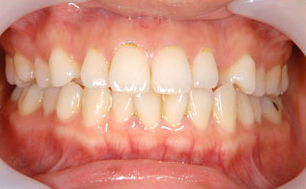

デュアルホワイトニング

の症例

| 年齢・性別 | 23歳・男性 |

| 治療期間 | 1ヶ月 |

| 治療内容 | デュアルホワイトニング |

| 治療本数 | 全顎 |

| 治療費用 | デュアルホワイトニング(77,000円(税込)) |

| 副作用等 | 効果には個人差があります。 術後、知覚過敏が生じることがありますが、 ほとんどの場合1〜2日で治まります。 既存のつめ物・かぶせ物は白くなりません。 効果は永久的ではなく徐々に色戻りします。 |